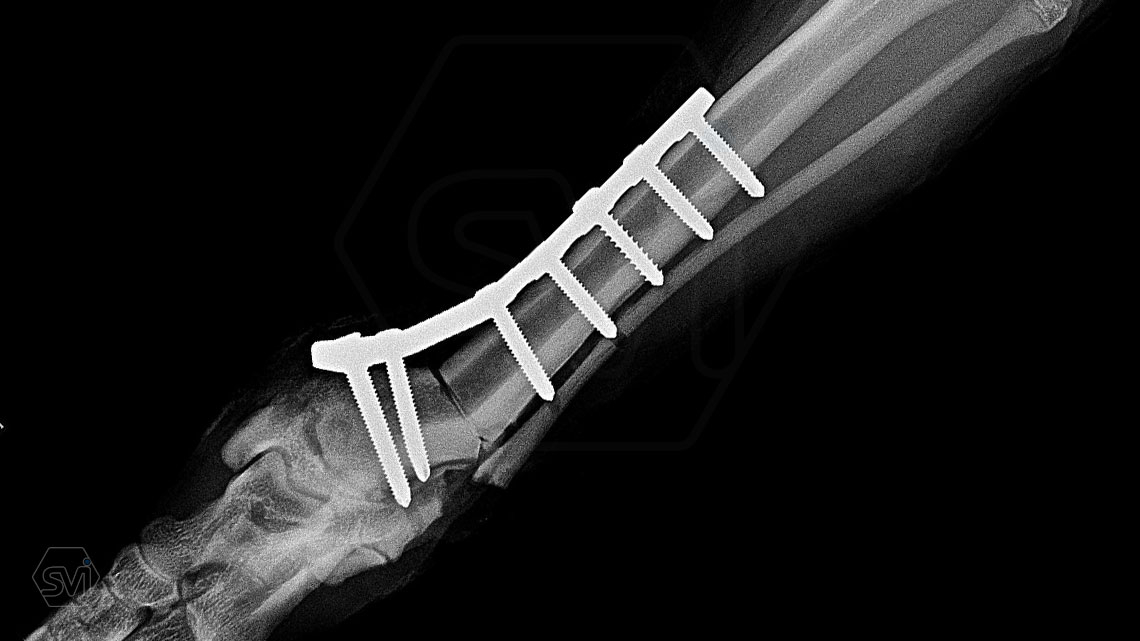

Multifunctional symmetrical long polyaxial locking plate - designed for the treatment of fractures close to joints

A special member of the polyaxial locking plate family is the multifunctional long plate, which is an extended version of the well-known symmetrical TPLO plate, with a 5-3 hole distribution. The plate also received a DCP hole to be able to create compression, and there is a mini-hole on the head end to facilitate the placement of the temporarily used K-nail. The burrs on the side facing the bone surface are intended to reduce the contact surface between the plate and the bone (limited contact).

The plate is a member of the large polyaxial locking family, suitable for 2.7-3.5-4.0 mm screws. We recommend it for fixaton of fractures close to joints, wedge osteotomies with axis correction (closing and opening), or for CWTO operations.